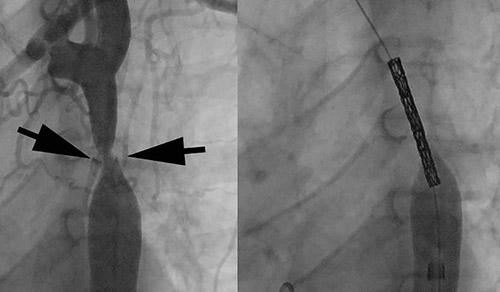

The patient’s severe thrombosis required months of multidisciplinary care and the transplantation of his liver, stomach, large intestine, small intestine, pancreas, and kidney.